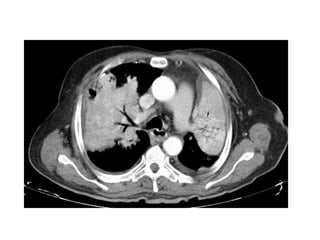

Multinodular pattern with foci of calcifications within one of

Multinodular pattern with cavitation of some nodules